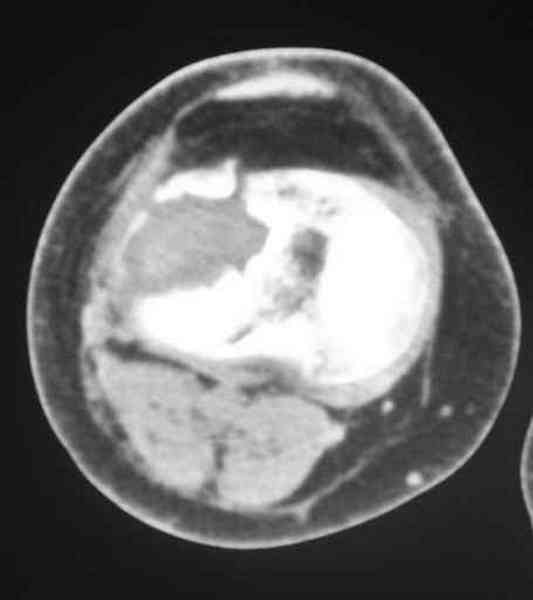

Обратился больной 46л. 3-месяца назад в каком-то городке Дальнего Востока упал с высоты, сделана Р-графия, наложена гипсовая повязка, от предложенной операции отказался и уехал домой, дальше где и как лечился, не говорит.

Ходит при помощи двух костылей, жалобы на боли при нагрузке, в покое и при движении, без нагрузке боли нет, разгибание 175 гр, сгибание 90 гр, симптомов повреждения связочного аппарата к/с не определяется, от предложенного артродеза пока отказывается.

Уважаемые коллеги! какие будут мнения по поводу лечения, эндопротез недоступен. Заранее благодарю! С уважением Абдурашид.

По тактике лечения, более импонирует второй вариант, но наружная плато расколота и туда при нагрузке внедряется н/мышелка бедра, поэтому после дистракции как репонирвать: или стяжными винтами, или изогнутами спицами или субхондральная костная пластика?

Уважаемый Абдурашид. Если нет противопоказаний , то из оперативных способов, я бы рекомендовал следующие: Полное замещение наружного мыщелка аллотрансплантатом либо открытая репозиция с элевацией и замещение дефекта ауто или аллокостью. В Ваших условиях , я бы рекомендовал второй способ. Во-время элевации необходимо разъединить фрагменты со стороны сустава ( надсечь скальпелем по линиям перелома, а затем тонким остеотомом их разъединить. При помощи долота произвести неполную остеотомию ( захватите не менее 1,5 - 2 см губчатой кости и поднять фрагменты, визуально отрепонировать и фиксировать 2-3 спицами. Дефект заместить костным ауто или аллатрансплантатом. Окончательная стабилизация пластиной ( лучше с угловой стабильностью, либо АВФ - позволит спокойно устранить угловую деформацию.

У пациента основной проблемой является импрессионый перелом наружного мыщелка, уже неправильно сросшийся, по-видимому. Аппаратом закрыто можно только подправить угол на уровне метадиафиза. Что

улучшит разве что внешний вид конечности, но не решит основной проблемы - грубой деформации суставной поверхности.